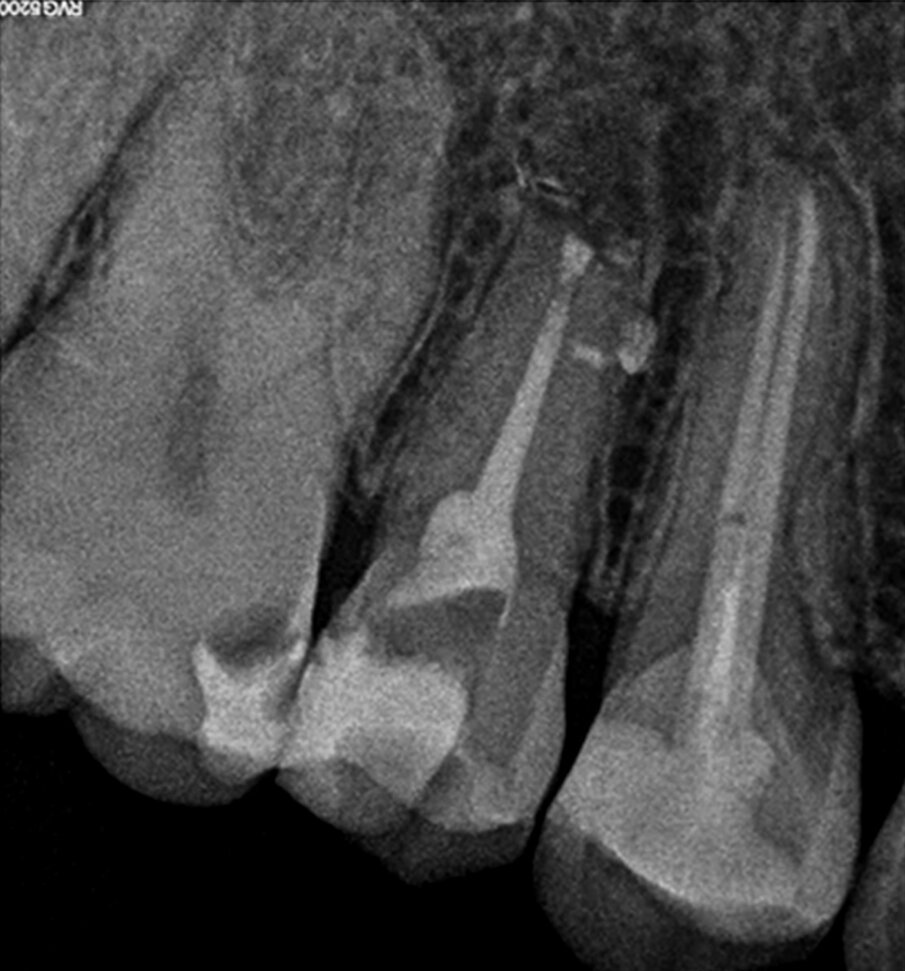

A 38-year-old female patient consulted owing to moderate pain associated with her previously treated maxillary right second premolar. Her medical history was non-contributory. Clinical examination revealed that the tooth was slightly sensitive to vertical percussion. Periodontal probing depth and mobility were within normal limits. A periapical radiograph showed the presence of a separated instrument outside of the root (Fig. 2a), and a preoperative CBCT scan demonstrated that the buccal bone plate was intact (Figs. 2b & c). Endodontic retreatment had been performed five months earlier. The diagnosis for tooth #15 was previously treated symptomatic periapical periodontitis, and the treatment of choice was guided EMS.

Fig. 2k: Post-op radiograph after apicectomy, retro-preparation and retro-filling with TotalFill BC RRM Fast Set Putty.

Fig. 2m: Two years follow-up radiograph.